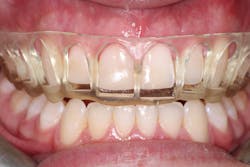

New scans of the patient’s mouth were taken eight weeks after the osseous surgery, prior to the minimal veneer preparations. The original digital plan then can be evaluated, which typically involves minor changes. The next phase design would be printed in the office following sharing the STL files (stereolithography). This allows the office to create a restorative matrix and reduction guide for the dentist. Careful preparation was utilized so as to stay within enamel only, which many studies have shown allows for more predictable bonding and longevity of veneer restorations. Standard tissue retraction methods were used, and the preps were scanned with iTero 5D Plus. The provisionals created from the digital plan would allow the patient to test-drive the new smile prior to the final 10 porcelain restorations being placed. The patient was seen a few days after his preps to allow any modifications before the final 10 e.max pressable veneers were created.

After experiencing the comparative advantage the provisional teeth offered him, the patient was ready for the final restorations to be placed. After placement, the patient left the office with both an esthetic and functional upgrade to take on life after college with confidence, featuring 10 porcelain veneers across his maxillary teeth.